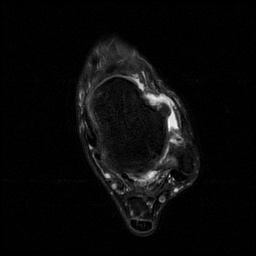

患者,男,28岁,有踝关节扭伤史,患者10天前扭伤致左踝疼痛伴活动受限。查体:左踝关节轻度肿胀,关节缘广泛性压痛,未扪及骨擦音及骨擦感,局部皮肤无瘀青、无皮损,外翻应力试验阳性,抽屉试验阳性,肢端感觉及血运正常。

患者行关节镜下距腓前韧带修补术,术后恢复良好。